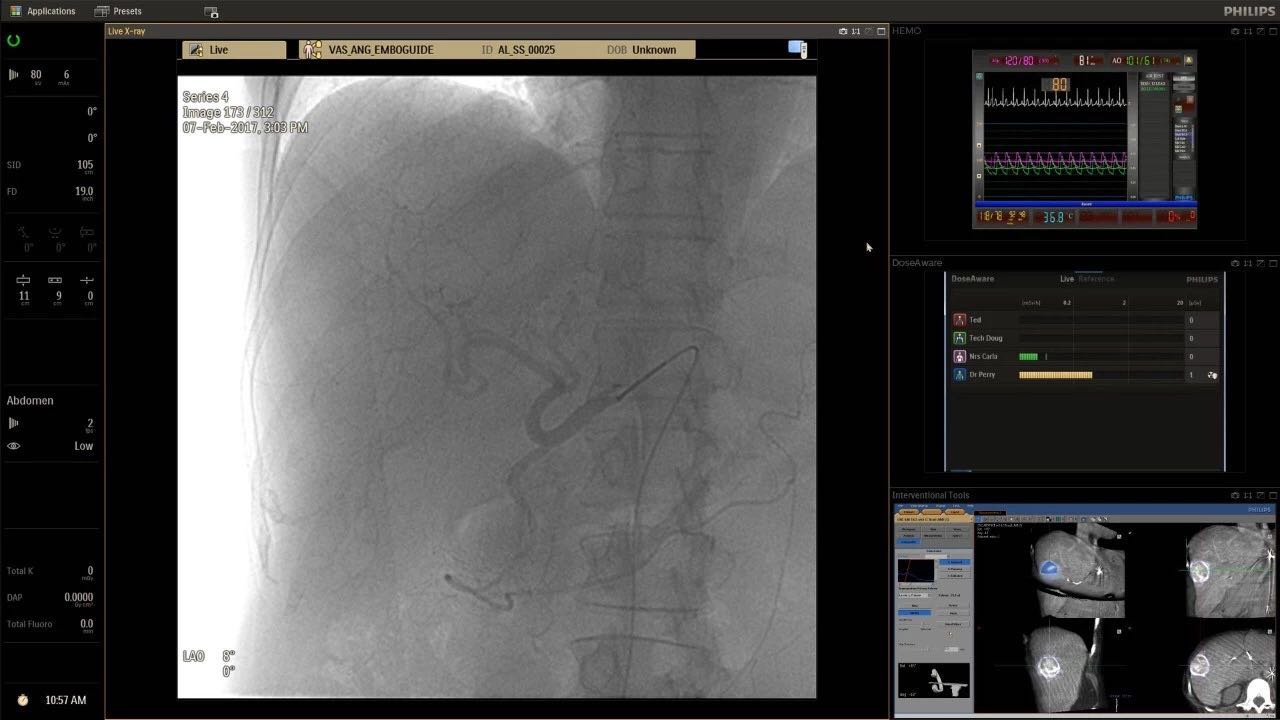

帶有FlexArm的Azurion 7 C20 包含一系列創(chuàng)新技術(shù),使臨床醫(yī)生可以更輕松地在整個(gè)患者身上進(jìn)行二維和三維成像。當(dāng)臨床醫(yī)生移動(dòng)系統(tǒng)時(shí),圖像光束自動(dòng)保持與患者的對準(zhǔn),允許更一致的可視化并使他們能夠?qū)⒆⒁饬性谥委熒稀?/span>

可通過微創(chuàng)手術(shù)治療的疾病的范圍和復(fù)雜性繼續(xù)擴(kuò)大。相應(yīng)地,程序本身也變得更加復(fù)雜,需要來自不同學(xué)科的更多醫(yī)生在患者的桌邊,以高度協(xié)調(diào)的方式一起工作。因此,臨床團(tuán)隊(duì)需要在高度受限的環(huán)境中執(zhí)行越來越具有挑戰(zhàn)性的程序。

飛利浦表示,采用FlexArm設(shè)計(jì)的Azurion 7 C20可提供卓越的靈活性和直觀的控制。該系統(tǒng)由智能運(yùn)動(dòng)引擎驅(qū)動(dòng),可在八個(gè)不同的軸上移動(dòng),所有這些軸均由其單個(gè)“Axsys”控制器控制。臨床醫(yī)生的模擬測試表明,該系統(tǒng)有可能顯著減少患者,工作人員和設(shè)備的重新定位,從而改善微創(chuàng)手術(shù)的可及性,包括通過患者手腕進(jìn)入身體的手術(shù)(橈動(dòng)脈入路),并降低患者的風(fēng)險(xiǎn)。無意中拔出電線和管子,以及節(jié)省大量時(shí)間。該系統(tǒng)非常適合混合手術(shù)室(OR),可滿足一個(gè)房間內(nèi)的多種專業(yè)需求,例如手術(shù)和血管內(nèi)手術(shù)的組合。